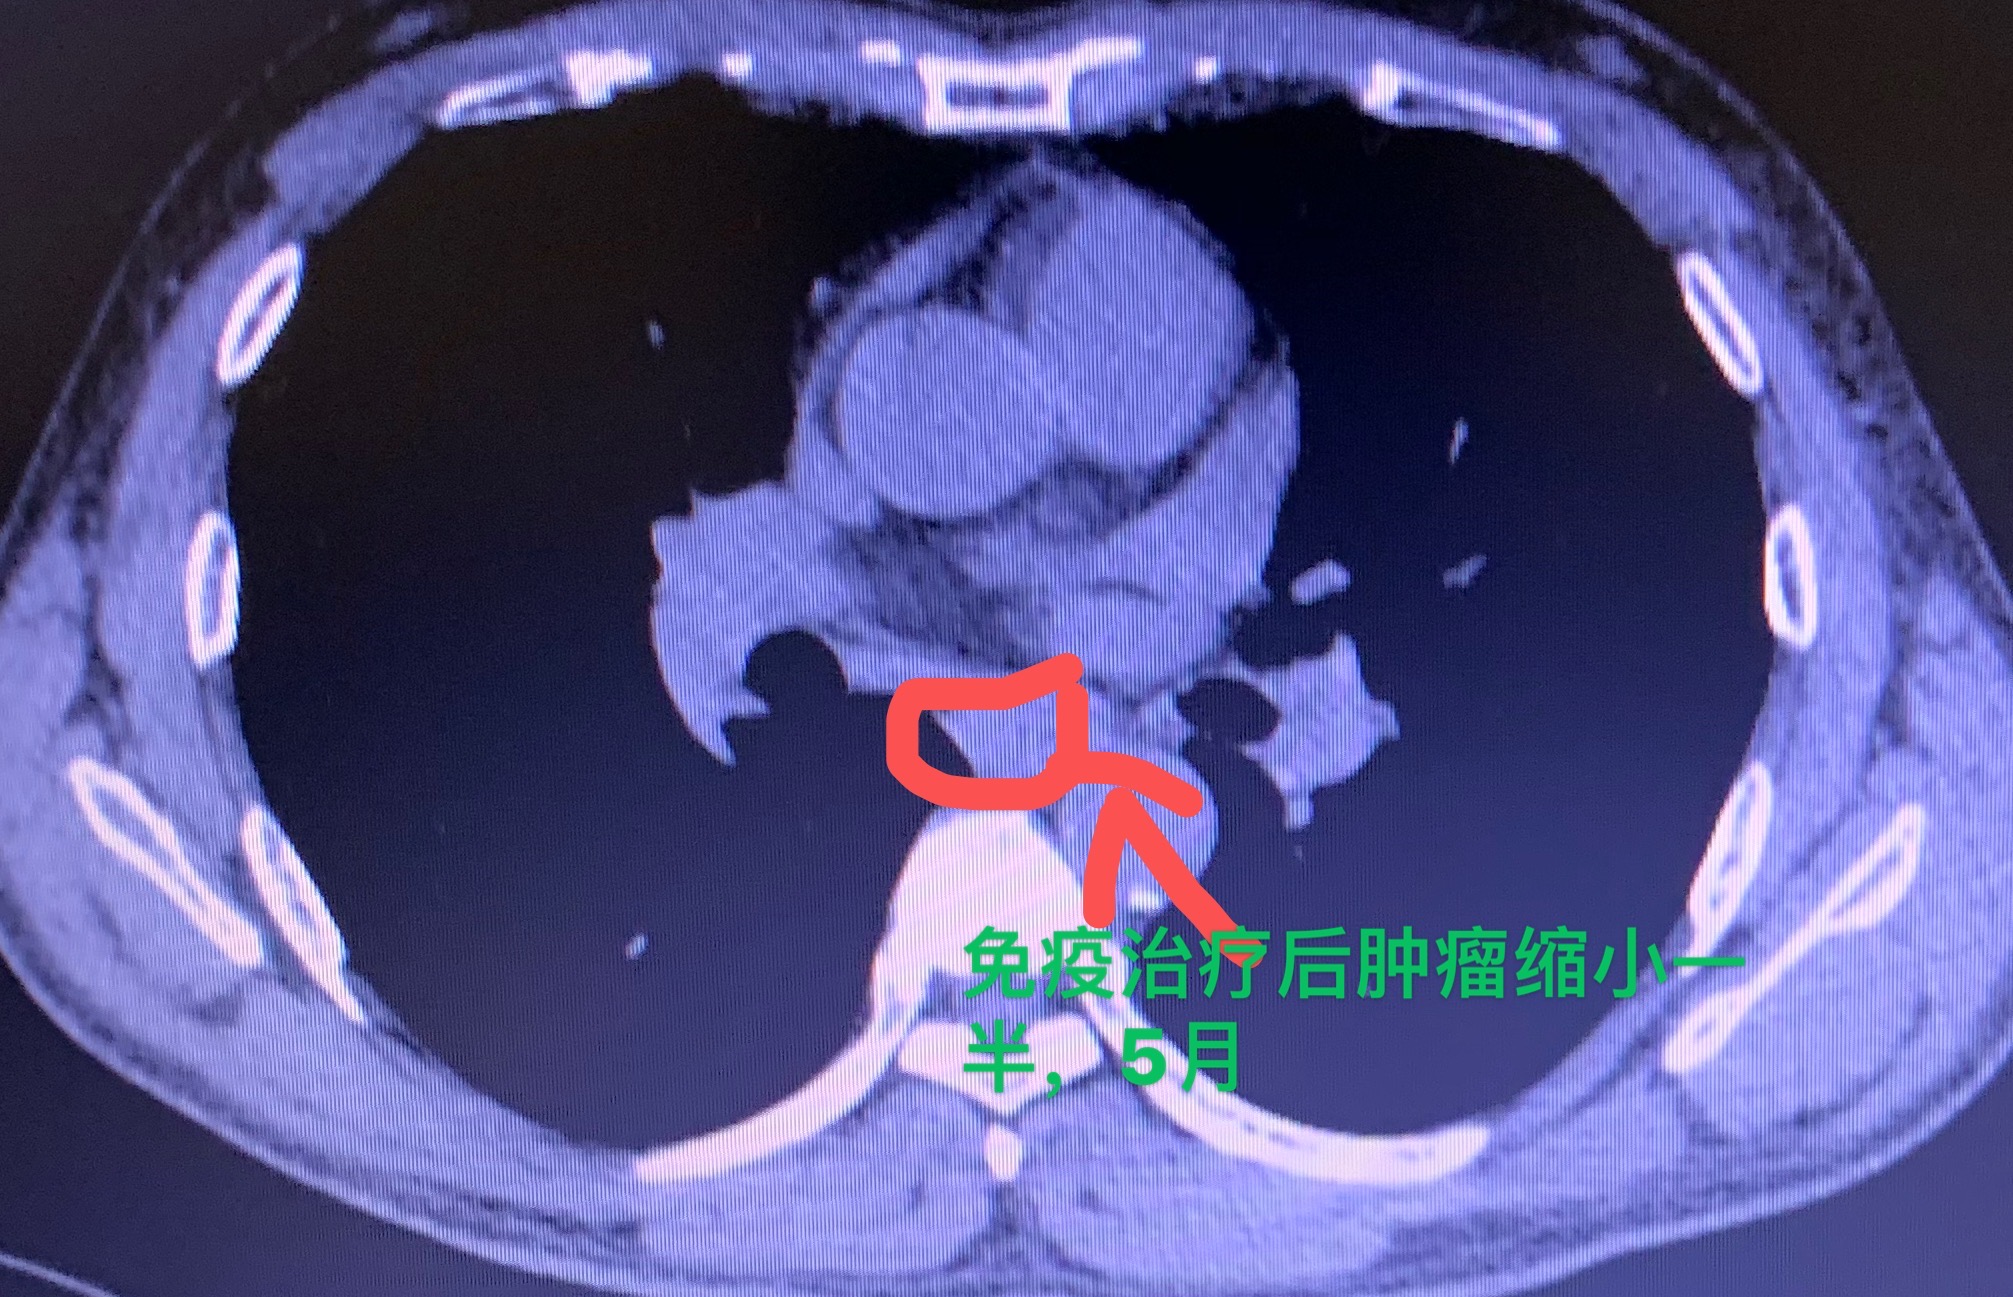

免疫治疗肿瘤减小一半, 为手术带来机会

食管癌不但影响身体健康、影响生命,而且会使人的生活质量变得很差。患了食...